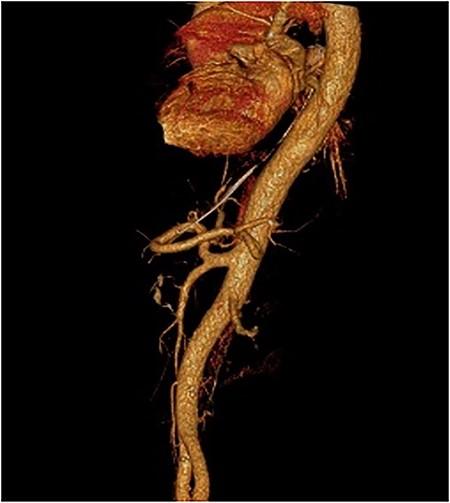

After the negative GI endoscopy for active bleeding, contrast-enhanced CT in the arterial phase was performed and revealed a pseudoaneurysm of the gastroduodenal artery with a diameter of 9 mm, and a second smaller pseudoaneurysm of a branch of gastroduodenal artery were demonstrating (Fig. 4). Furthermore, celiac-mesenteric trunk and worsening image of pancreatitis were depicted (Fig. 5). After that, emergency embolization of the pseudoaneurysms was performed, using a 4-F arterial sheath via the Seldinger technique. A celiac angiogram was obtained with a 4-F angiographic catheter type Cobra (Medical Materials, Boynton Beach, Florida, USA). Using microcatheter Asahi Caravel (Asahi-Intecc USA Medical, Tustin, California, USA), microcatheter SwiftNinja (Merit Medical, South Jordan, Utah, USA) and microcoils of (Boston Scientific, Marlborough, Massachusetts, USA) 2.5 and 3 mm, complete embolization of the two pseudoaneurysms was achieved (Fig. 6).

Contrast-enhanced CT in arterial phase. A pseudoaneurysm of gastroduodenal artery with a diameter of 9 mm (white arrow). B. Smaller pseudoaneurysm of a branch of gastroduodenal artery (white arrow).